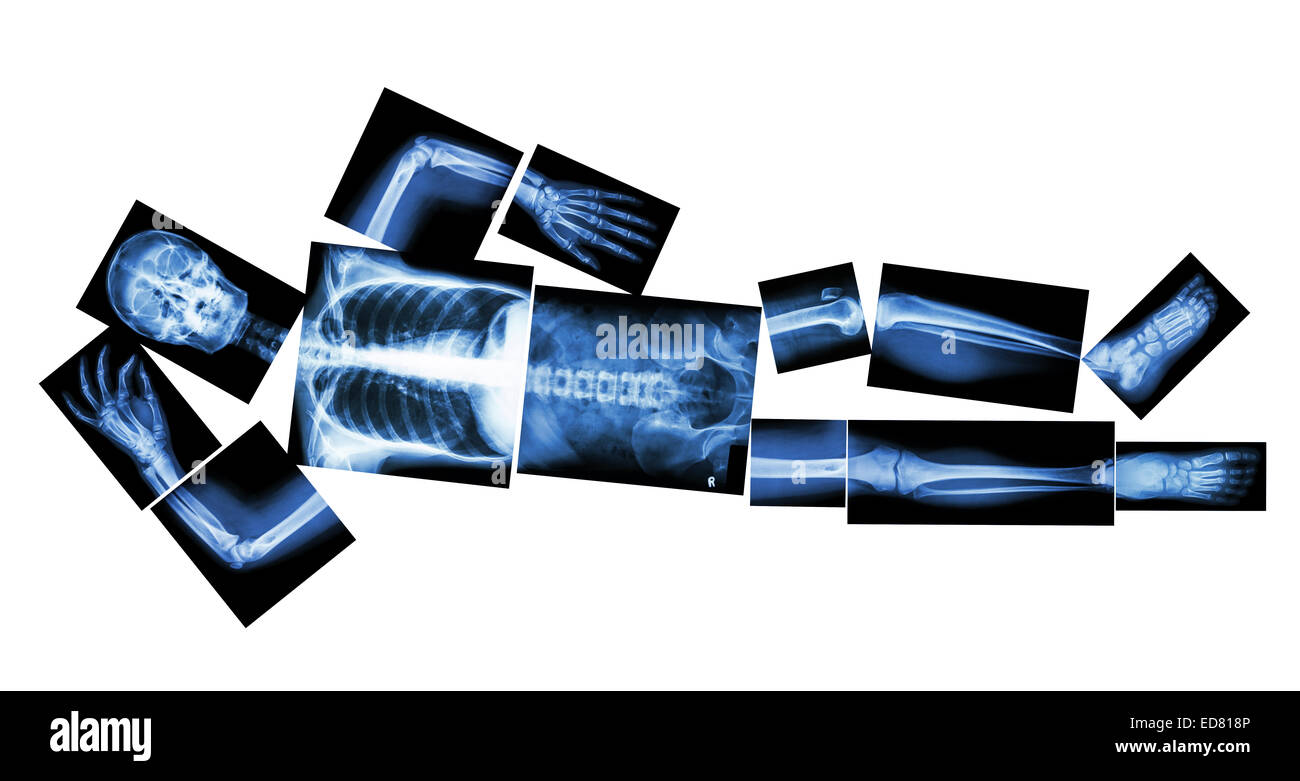

Marathon (les droits de l'os est en marche) ,(corps entier x-ray : tête, cou, bras, épaule, coude, avant-bras, main, doigt ,,commune thorax ,ab Banque D'Imageshttps://www.alamyimages.fr/image-license-details/?v=1https://www.alamyimages.fr/photo-image-marathon-les-droits-de-l-os-est-en-marche-corps-entier-x-ray-tete-cou-bras-epaule-coude-avant-bras-main-doigt-commune-thorax-ab-77324375.html

Marathon (les droits de l'os est en marche) ,(corps entier x-ray : tête, cou, bras, épaule, coude, avant-bras, main, doigt ,,commune thorax ,ab Banque D'Imageshttps://www.alamyimages.fr/image-license-details/?v=1https://www.alamyimages.fr/photo-image-marathon-les-droits-de-l-os-est-en-marche-corps-entier-x-ray-tete-cou-bras-epaule-coude-avant-bras-main-doigt-commune-thorax-ab-77324375.htmlRFEDPC0R–Marathon (les droits de l'os est en marche) ,(corps entier x-ray : tête, cou, bras, épaule, coude, avant-bras, main, doigt ,,commune thorax ,ab

Marathon (les droits de l'os est en marche) ,(corps entier x-ray : tête, cou, bras, épaule, coude, avant-bras, main, doigt ,,commune thorax ,ab Banque D'Imageshttps://www.alamyimages.fr/image-license-details/?v=1https://www.alamyimages.fr/photo-image-marathon-les-droits-de-l-os-est-en-marche-corps-entier-x-ray-tete-cou-bras-epaule-coude-avant-bras-main-doigt-commune-thorax-ab-77324374.html

Marathon (les droits de l'os est en marche) ,(corps entier x-ray : tête, cou, bras, épaule, coude, avant-bras, main, doigt ,,commune thorax ,ab Banque D'Imageshttps://www.alamyimages.fr/image-license-details/?v=1https://www.alamyimages.fr/photo-image-marathon-les-droits-de-l-os-est-en-marche-corps-entier-x-ray-tete-cou-bras-epaule-coude-avant-bras-main-doigt-commune-thorax-ab-77324374.htmlRFEDPC0P–Marathon (les droits de l'os est en marche) ,(corps entier x-ray : tête, cou, bras, épaule, coude, avant-bras, main, doigt ,,commune thorax ,ab

Marathon (les droits de l'os est en marche) ,(corps entier x-ray : tête, cou, bras, épaule, coude, avant-bras, main, doigt ,,commune thorax ,ab Banque D'Imageshttps://www.alamyimages.fr/image-license-details/?v=1https://www.alamyimages.fr/photo-image-marathon-les-droits-de-l-os-est-en-marche-corps-entier-x-ray-tete-cou-bras-epaule-coude-avant-bras-main-doigt-commune-thorax-ab-77323572.html

Marathon (les droits de l'os est en marche) ,(corps entier x-ray : tête, cou, bras, épaule, coude, avant-bras, main, doigt ,,commune thorax ,ab Banque D'Imageshttps://www.alamyimages.fr/image-license-details/?v=1https://www.alamyimages.fr/photo-image-marathon-les-droits-de-l-os-est-en-marche-corps-entier-x-ray-tete-cou-bras-epaule-coude-avant-bras-main-doigt-commune-thorax-ab-77323572.htmlRFEDPB04–Marathon (les droits de l'os est en marche) ,(corps entier x-ray : tête, cou, bras, épaule, coude, avant-bras, main, doigt ,,commune thorax ,ab

Marathon (les droits de l'os est en marche) ,(corps entier x-ray : tête, cou, bras, épaule, coude, avant-bras, main, doigt ,,commune thorax ,ab Banque D'Imageshttps://www.alamyimages.fr/image-license-details/?v=1https://www.alamyimages.fr/photo-image-marathon-les-droits-de-l-os-est-en-marche-corps-entier-x-ray-tete-cou-bras-epaule-coude-avant-bras-main-doigt-commune-thorax-ab-77324380.html

Marathon (les droits de l'os est en marche) ,(corps entier x-ray : tête, cou, bras, épaule, coude, avant-bras, main, doigt ,,commune thorax ,ab Banque D'Imageshttps://www.alamyimages.fr/image-license-details/?v=1https://www.alamyimages.fr/photo-image-marathon-les-droits-de-l-os-est-en-marche-corps-entier-x-ray-tete-cou-bras-epaule-coude-avant-bras-main-doigt-commune-thorax-ab-77324380.htmlRFEDPC10–Marathon (les droits de l'os est en marche) ,(corps entier x-ray : tête, cou, bras, épaule, coude, avant-bras, main, doigt ,,commune thorax ,ab